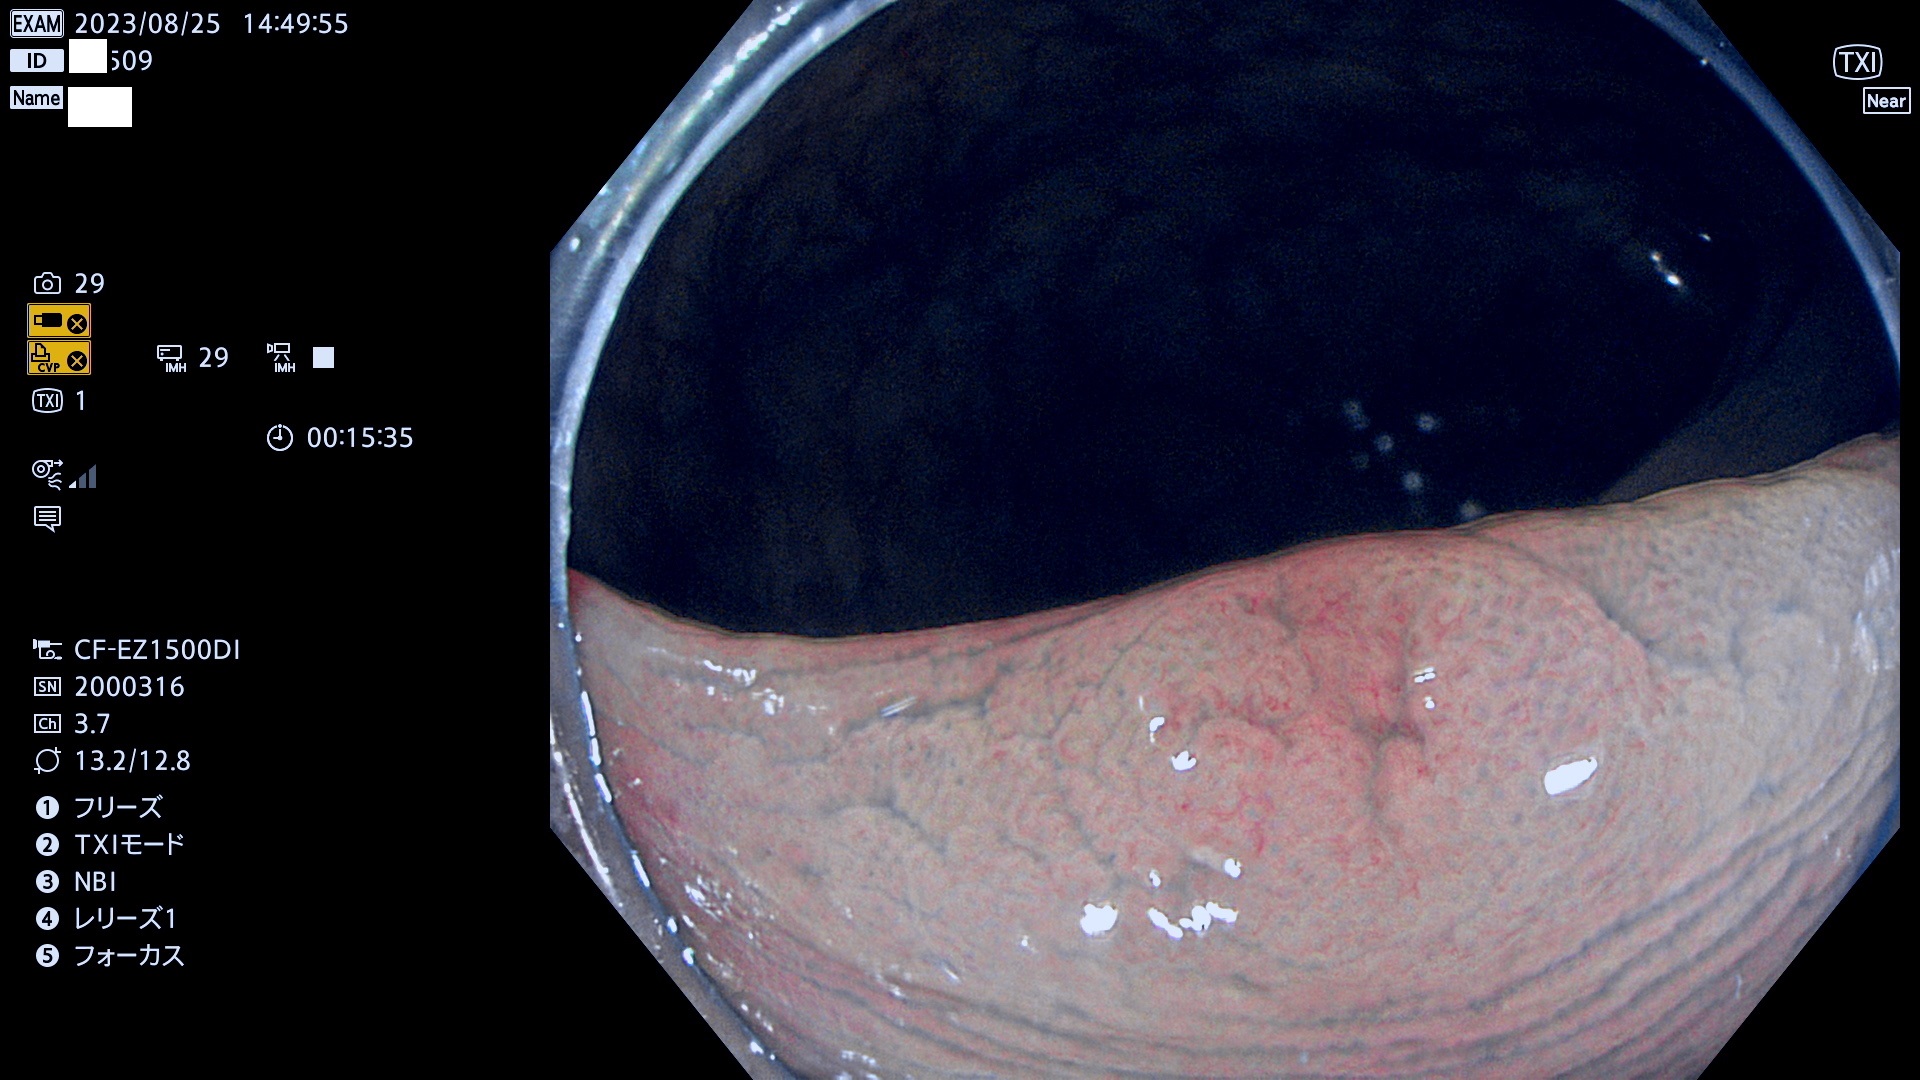

表面型腺腫(Flat Adenoma)の中で、完全に平坦な物をUb、陥凹している物をUcと呼びます。平坦隆起型(Ua)よりも、発見が難しく危険な病変です。このタイプは「内視鏡後・大腸癌の重要犯人」であり、この発見率は「腺腫発見率」よりも、重要な意味があります。

毎週の検査(木・金・土・日)に発見されたUb、Uc型・腺腫を、その週の日曜の夜にUPし1週間、提示します。

抽出の対象期間 2023年8月24日(木)〜8月27(日)の4日間(48件の検査)9件